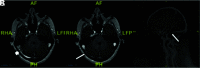

Background and purpose: Dural venous sinus stenosis has been associated with idiopathic intracranial hypertension and isolated venous pulsatile tinnitus. However, the utility of characterizing stenosis as intrinsic or extrinsic remains indeterminate. The aim of this retrospective study was to review preprocedural imaging of patients with symptomatic idiopathic intracranial hypertension and pulsatile tinnitus, classify the stenosis, and assess a trend between stenosis type and clinical presentation while reviewing the frequencies of other frequently seen imaging findings in these conditions.

Materials and methods: MRVs of 115 patients with idiopathic intracranial hypertension and 43 patients with pulsatile tinnitus before venous sinus stent placement were reviewed. Parameters recorded included the following: intrinsic or extrinsic stenosis, prominent emissary veins, optic nerve tortuosity, cephalocele, sella appearance, poststenotic fusiform enlargement versus saccular venous aneurysm, and internal jugular bulb diverticula. χ2 cross-tabulation statistics were calculated and recorded for all data.

Results: Most patients with idiopathic intracranial hypertension (75 of 115 sinuses, 65%) had extrinsic stenosis, and most patients with pulsatile tinnitus (37 of 45 sinuses, 82%) had intrinsic stenosis. Marked optic nerve tortuosity was more common in idiopathic intracranial hypertension. Cephaloceles were rare in both cohorts, with an increased trend toward the presence in idiopathic intracranial hypertension. Empty sellas were more common in idiopathic intracranial hypertension. Cerebellar tonsils were similarly located at the foramen magnum level in both cohorts. Saccular venous aneurysms were more common in pulsatile tinnitus. Internal jugular bulb diverticula were similarly common in both cohorts.

Conclusions: In this cohort, most patients with idiopathic intracranial hypertension had extrinsic stenosis, and most patients with pulsatile tinnitus had intrinsic stenosis. Awareness and reporting of these subtypes may reduce the underrecognition of potential contributory stenoses in a given patient's idiopathic intracranial hypertension or pulsatile tinnitus.